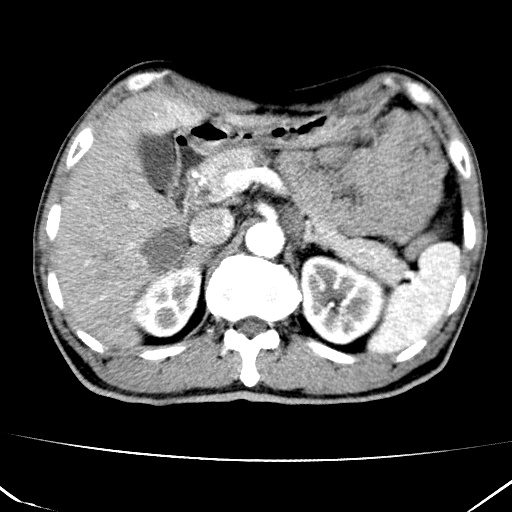

标题: CT17975:请求会诊。男、57岁。上腹部胀痛2天。临床诊断:糜 [打印本页]

标题: CT17975:请求会诊。男、57岁。上腹部胀痛2天。临床诊断:糜

肝脏多发类圆形低密度影,考虑肝脏转移瘤,肝胃韧带一淋巴结肿大,原发?胃癌?

考虑胃癌肝脏转移可能性大。

考虑胃癌并肝脏及腹膜后淋巴结转移;不排除淋巴瘤。

肝内转移瘤,腹腔及腹膜后淋巴结转移。